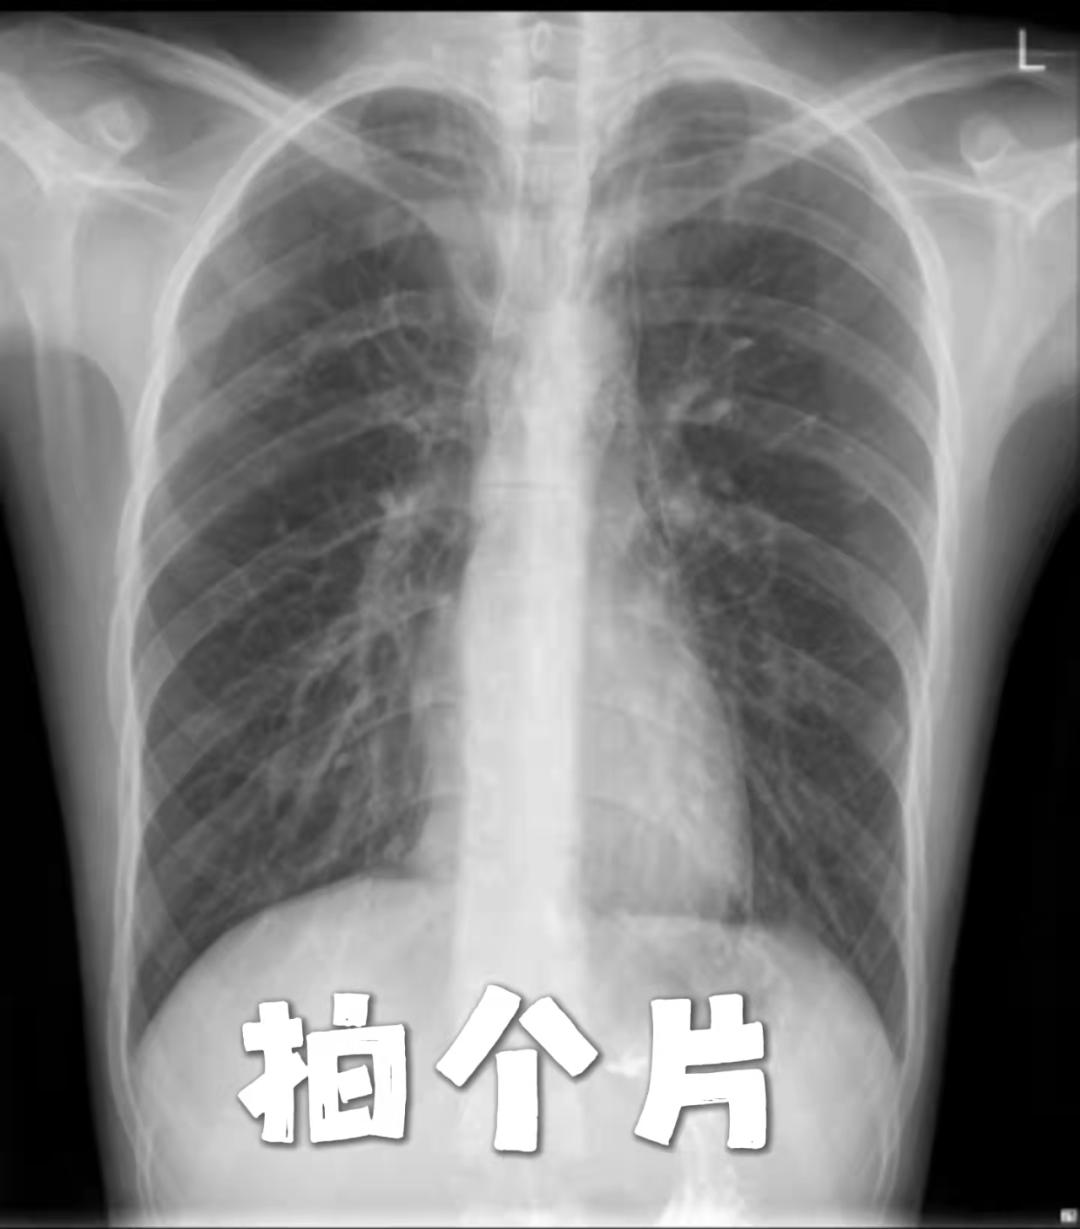

这是一位

纵隔气肿患者的检查报告

经胸部CT可见横断位螺旋扫描层厚5mm,层距5mm。胸廓对称,气管居中,肺支气管血管束规整,未见异常组织密度影及占位性病变。气管、支气管通畅,未见狭窄或阻塞征,肺门影不大。纵隔内及颈根部见散在游离气体密度影。双侧胸膜无增厚,用真实有效的报告确诊了纵隔气肿。